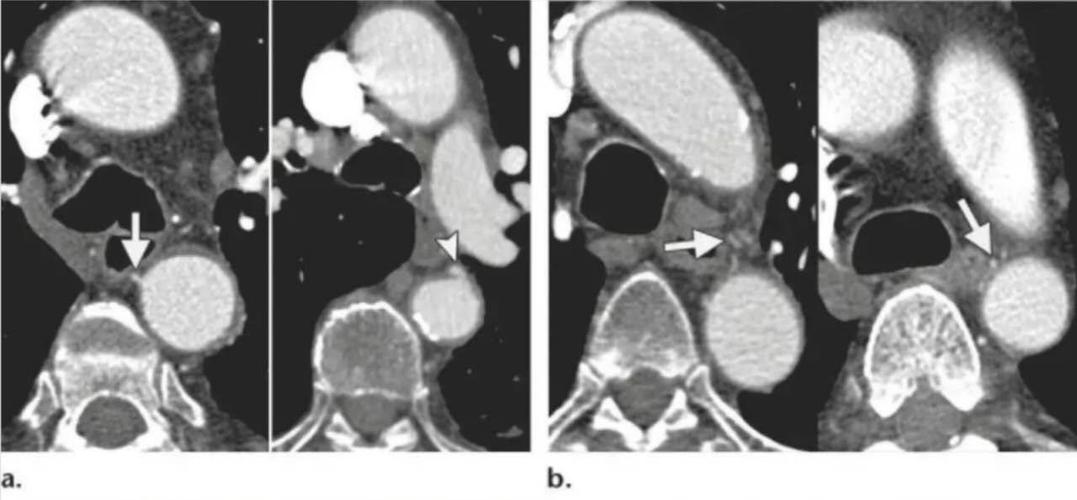

正常人支气管内经小于伴行动脉直径,支扩患者的支气管比伴行动脉粗